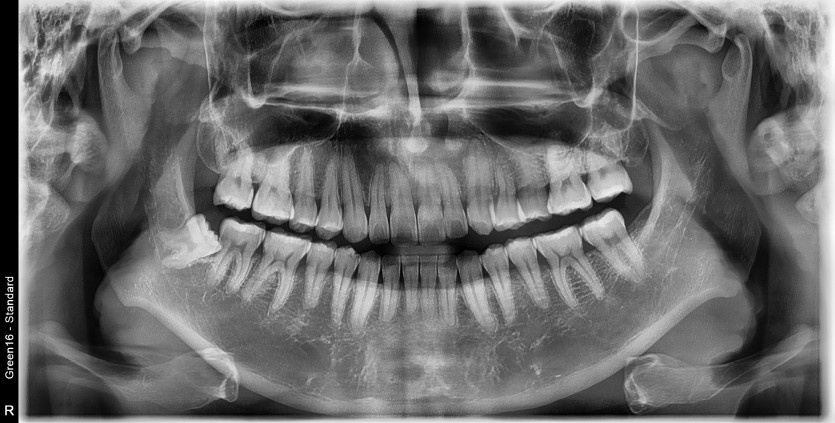

#48 사랑니 발치

구강 외과 전문의가 당일 발치했습니다.